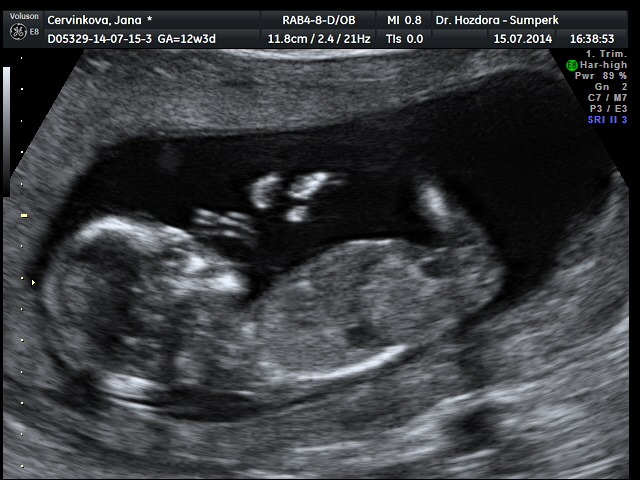

Děvčata,tak jsem doma z ultrazvuku,ten dopadl skvěle,šíjové projasnění,nosní kůstka,vše tak,jak má být. Dnes jsem 12+3,ale podle ultrazvuku už 13+1. Vypadá to pravděpodobně,že čekáme holčičku,ale jistější to bude ve 20.tt. Zítra mi sestry zavolají,jak dopadly krevní odběry...zatím mám z toho skvělý pocit. A docela mimo je i můj chlap,moc se nevyjadřoval,on ty pocity dusí v sobě,ale vypadal spokojeně. Tak zítra se screening zkompletuje a věřím,že to bude v cajku. Určitě dám zítra vědět..